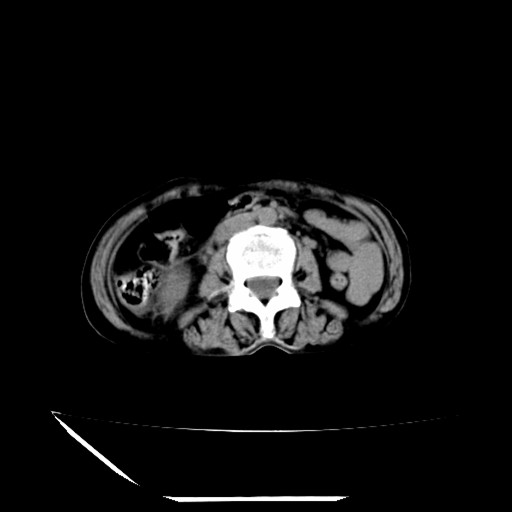

标题: CT16840:女-63岁,下腹部疼痛, [打印本页]

标题: CT16840:女-63岁,下腹部疼痛,

补充资料:血象是13.5,临床拟诊阑尾炎

本人诊断是右肾周围炎,阑尾炎,盆腔少许积液!

诊断右肾周围炎是因为我图像没有发完,诊断阑尾炎是因为相当于阑尾区连续两个层面可以看到增粗的阑尾显影。

支持阑尾炎!局部腹膜增厚,脂肪密度增高。应该手术治疗。